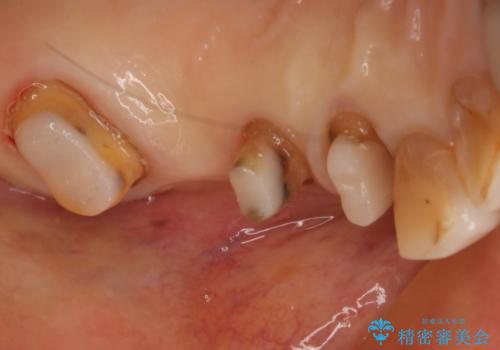

古い被せ物を除去し、中の状態をキレイにしたうえで改めて金属を使用していない被せ物で噛み合わせの回復を行いました。

被せ物の色は噛み合う反対側の被せ物と合わせて作りました。